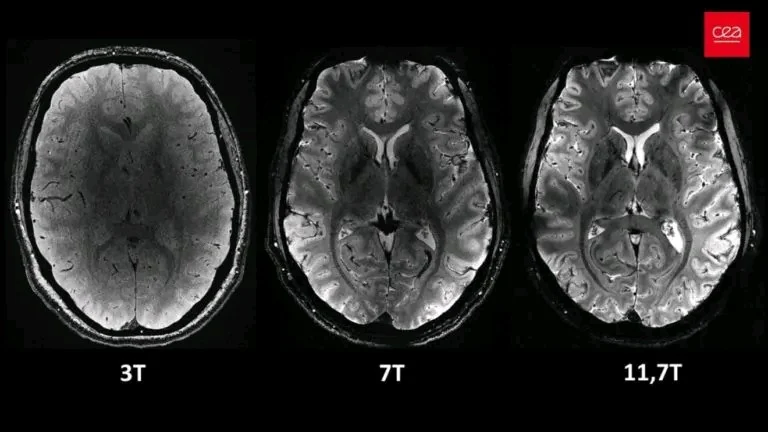

Imagens comparativas do cérebro humano tiradas com o novo scanner de ressonância magnética da Iseult em diferentes níveis de potência – 3 Tesla (T), 7 T e 11,7 T – todas tiradas no mesmo período de tempo, mostrando a quantidade de detalhes extras produzidos em maior potência. © CEA

A ressonância magnética de Iseult opera a uma potência magnética máxima de 11,7 Tesla (T), que é excepcionalmente alta em comparação com os scanners de ressonância magnética convencionais. Normalmente, os scanners operam com intensidades de campo magnético muito mais baixas, tipicamente em torno de 1,5 T e 3 T.

Este alto poder magnético garante uma melhor qualidade de imagem. A resolução espacial da varredura é de 200 micrômetros (μm), o que significa que o instrumento pode identificar dois pontos que estão a apenas 200 μm de distância. Essa alta resolução proporciona imagens mais estruturadas e precisas, permitindo que os médicos realizem exames com mais eficiência.